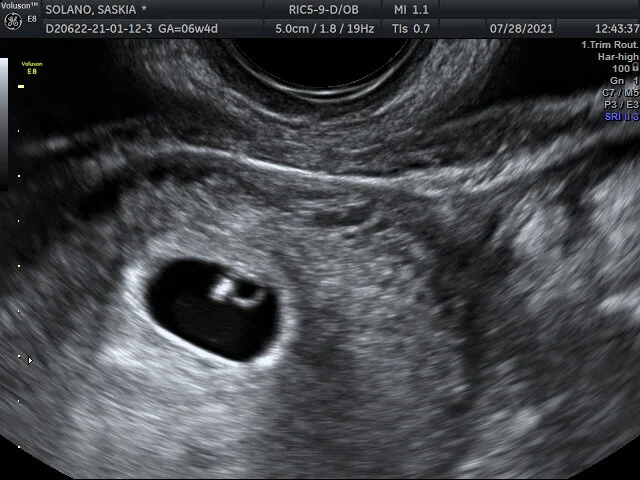

28 julio 2021

6 semanas, 0 días

• Tamaño: 0.35cm

• Latido del Corazón: 108 bpm

• Día de Nacimiento Esperado: 03/23/2022

Saskia y yo vamos a la cita con la Dr. Kim. Se hace un ultrasonido donde se ve y se mide el embrión, se escucha el latido del corazón, y se determina ajustar la fecha esperada de nacimiento. Efectivamente se atrasa 4 días. En vez de tener 6 semanas y 4 días, ahora se empieza a contar cómo si se tuviera sólo 6 semanas. Se debe utilizar la progesterona, una en el día y dos en la noche. Se debe seguir tomando el ácido fólico y se añaden vitaminas prenatales. Todavía no se debe hacer ejercicio, solo caminatas. Se hace una cita para el 24 de agosto a las 10 AM y hay que llevar los exámenes de laboratorio.